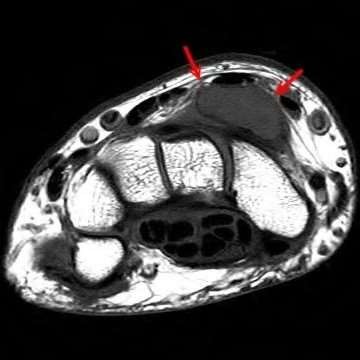

Question 14:

A 65-year-old male presents with deteriorating handwriting, dropping objects, and an unsteady, broad-based gait. On physical examination, flicking the volar nail of the middle finger results in an involuntary flexion reflex of the thumb and index finger. What is the name of this sign and its corresponding pathology?

Options:

- Wartenberg's sign - Ulnar neuropathy

- Hoffman's reflex - Cervical myelopathy

- Babinski reflex - Upper motor neuron lesion

- Lhermitte's sign - Multiple sclerosis

- Froment's sign - Anterior interosseous nerve syndrome

Correct Answer: Hoffman's reflex - Cervical myelopathy

Explanation:

The Hoffman's reflex is elicited by flicking the nail of the middle finger; a positive response is flexion of the IP joint of the thumb and index finger. It indicates an upper motor neuron lesion, classically cervical spondylotic myelopathy. Wartenberg's sign is the abducted posture of the small finger due to ulnar neuropathy. Lhermitte's sign is shock-like sensations down the spine with neck flexion. Froment's sign tests for ulnar nerve palsy (adductor pollicis weakness).